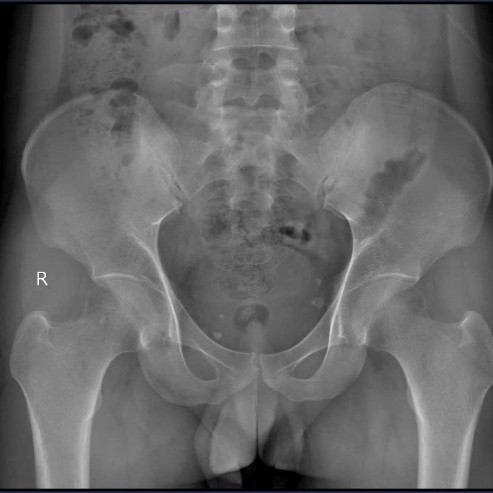

- X-quang khung chậu thẳng: viêm khớp cùng chậu độ III hai bên (theo tiêu chuẩn New York sửa đổi)

Viêm khớp cùng chậu hai bên độ III

< >Đặc điểm đau cột sống kiểu viêm: Đây là dấu hiệu then chốt để phân biệt với đau cột sống cơ học thông thường (do tư thế hoặc thoái hóa). Việc đau tăng về đêm và khi nghỉ và cải thiện khi vận động là đặc điểm của đau do bệnh lý khớp viêm, khác với tình trạng đau cột sống thông thường tăng khi vận động, sai tư thế và nghỉ ngơi thì đỡ đau. Việc nhận định sai tính chất của triệu chứng đau cột sống có thể làm chẩn đoán nhầm lẫn với bệnh lý đau cột sống thông thường.Xét nghiệm HLA-B27 dương tính: là xét nghiệm quan trọng trong chẩn đoán viêm cột sống dính khớp đặc biệt trong giai đoạn sớm khi bệnh nhân chưa có tổn thương trên Xquang, gặp ở 85-95% bệnh nhân viêm cột sống dính khớp.Viêm khớp cùng chậu trên XQuang: Mặc dù bệnh nhân đi khám vì đau cột sống cổ nhưng trong giai đoạn sớm có thể chưa có tổn thương về mặt cấu trúc trên Xquang cột sống cổ. Ngược lại, khớp cùng chậu thường là khớp có tổn thương thực thể đầu tiên trong viêm cột sống dính khớp do vậy chụp Xquang khớp cùng chậu là phương tiện quan trọng giúp chẩn đoán viêm cột sống dính khớp. Trong trường hợp của này bệnh nhân đã có viêm khớp cùng chậu độ III hai bên, cho thấy bệnh đã diễn tiến âm thầm một thời gian dài trước khi triệu chứng lâm sàng khiến bệnh nhân phải đi khám.Tránh biến chứng dính khớp: Nếu phát hiện muộn, các đốt sống sẽ dính lại với nhau thành “cột sống hình cây tre”, khiến bệnh nhân mất hoàn toàn khả năng vận động và gù vẹo, tàn phế và suy giảm chất lượng cuộc sống.Tiếp cận điều trị sớm: Việc phát hiện sớm khi còn ở giai đoạn viêm (chưa dính khớp) cho phép bác sĩ áp dụng các phác đồ tối ưu, bao gồm thuốc kháng viêm (NSAIDs) và đặc biệt là thuốc sinh học (kháng TNF hoặc kháng IL-17), giúp bệnh nhân ngăn chặn tổn thương cấu trúc và duy trì cuộc sống bình thường.